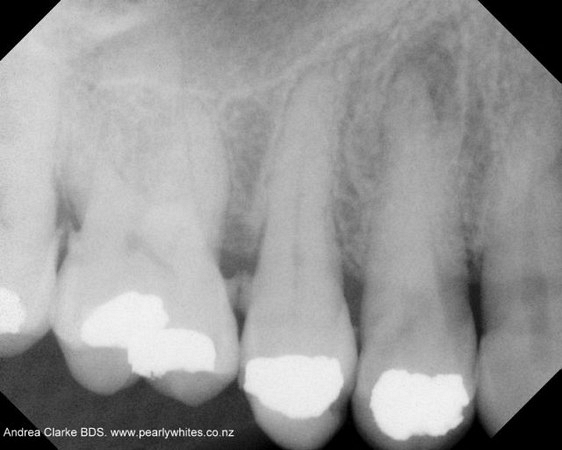

See xrays of before and after a root canal is completed below